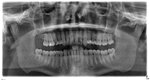

Als Anhang mal mein OPG von April 2008, die Karies im 16er wurde bereits im Kunststofffüllung bearbeitet, wonach das Speichelfluss-Problem übrigens auch wieder stärker wurde!

Als Anhang mal mein OPG von April 2008, die Karies im 16er wurde bereits im Kunststofffüllung bearbeitet, wonach das Speichelfluss-Problem übrigens auch wieder stärker wurde!